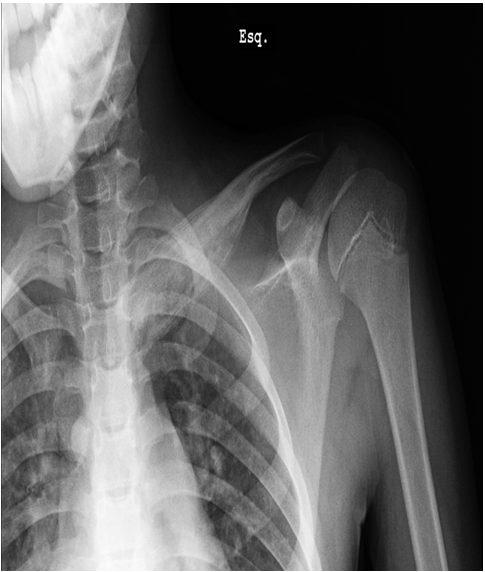

This is a case of an 11-year-old boy with left clavicle pain with two months of evolution presented to emergency department. No history of trauma, fever or systemic signs, recent illness and no relevant personal or familiar medical history. No neurological or vascular abnormalities were found in the upper arms. Left shoulder X-ray revealed a hyperdense lesion and increased thickness of left clavicle (Figure 1). In this context a computed tomography (CT) scan and after a magnetic resonance imaging (MRI) scan were ordered. Both scans demonstrated morphological changes of the median half of the clavicle, cortical destruction and periosteal reaction. Also changes in the surrounding soft and muscular tissue and bulky and numerous locoregional ganglion formations (Figure 2) and (Figure 3). Blood analysis, blood cultures and bone biopsy were negative for infection and neoplastic disorder. In this context, by exclusion, and in the presence of two Jansson major diagnostic criteria (radiologically proven osteolytic/osteosclerotic bone lesions and sterile bone biopsy with signs of inflammation) [1], we reached the diagnosis of chronic recurrent multifocal osteomyelitis (CMRO) (Table 1). Patient was treated with NSAIDs for six months and a short course of corticoids without any response. By keeping complaints of marked and recalcitrant pain in clavicle region, we opted for the surgical treatment: resection of the lesion en bloc, about 7 cm of clavicle (Figure 4), maintaining the integrity of periosteum to allow neo-osteogenesis of the clavicle. No bone grafting or another material was interposed in the dead space left by the resection of the clavicle. Post operatory X-ray, showing a radiopaque area corresponding to the excision of the medial portion of the clavicle (Figure 5).

Figure 2: Computed tomography scan morphological changes of the median half of the clavicle (increased thickness) and cortical destruction.